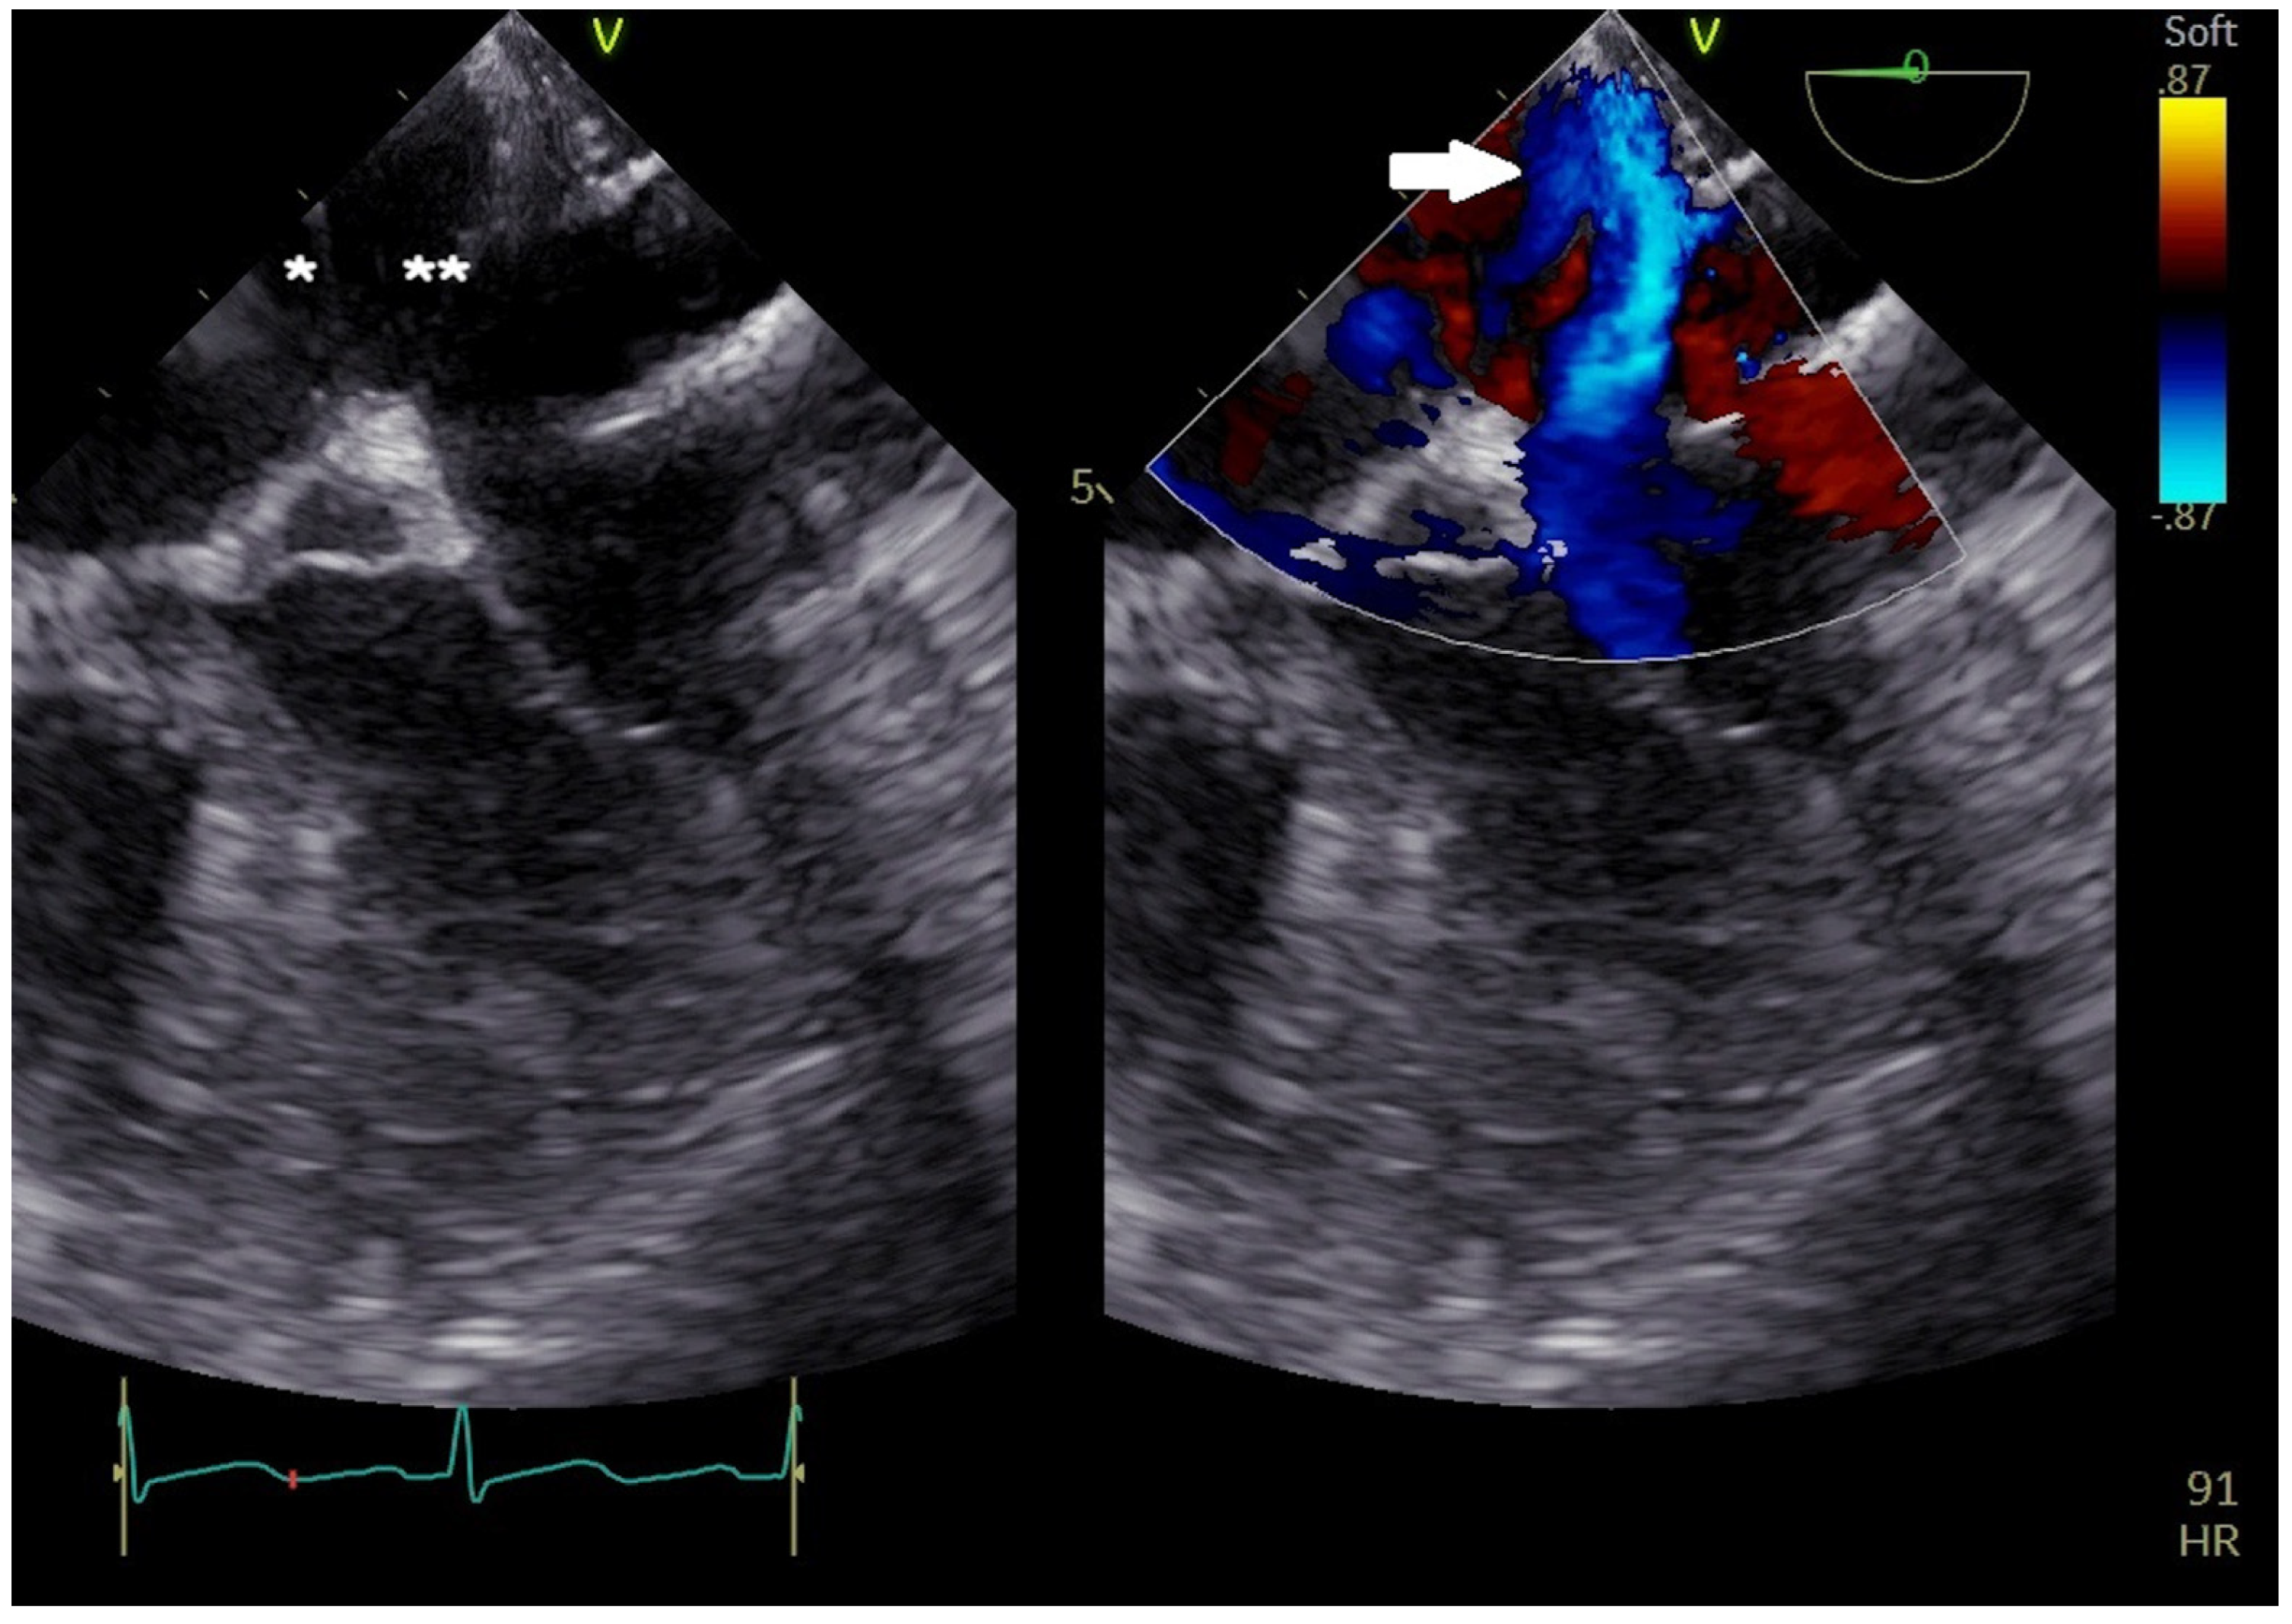

2. Atrial Septal Defect Closure